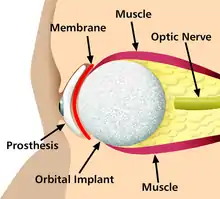

Some examples include pacemakers, infusion pumps, the heart-lung machine, dialysis machines, artificial organs, implants, artificial limbs, corrective lenses, cochlear implants, ocular prosthetics, facial prosthetics, somato prosthetics, and dental implants.

Implants

An implant is a kind of medical device made to replace and act as a missing biological structure (as compared with a transplant, which indicates transplanted biomedical tissue). The surface of implants that contact the body might be made of a biomedical material such as titanium, silicone or apatite depending on what is the most functional. In some cases, implants contain electronics, e.g. artificial pacemakers and cochlear implants. Some implants are bioactive, such as subcutaneous drug delivery devices in the form of implantable pills or drug-eluting stents.

Artificial body part replacements are one of the many applications of bionics. Concerned with the intricate and thorough study of the properties and function of human body systems, bionics may be applied to solve some engineering problems. Careful study of the different functions and processes of the eyes, ears, and other organs paved the way for improved cameras, television, radio transmitters and receivers, and many other tools.